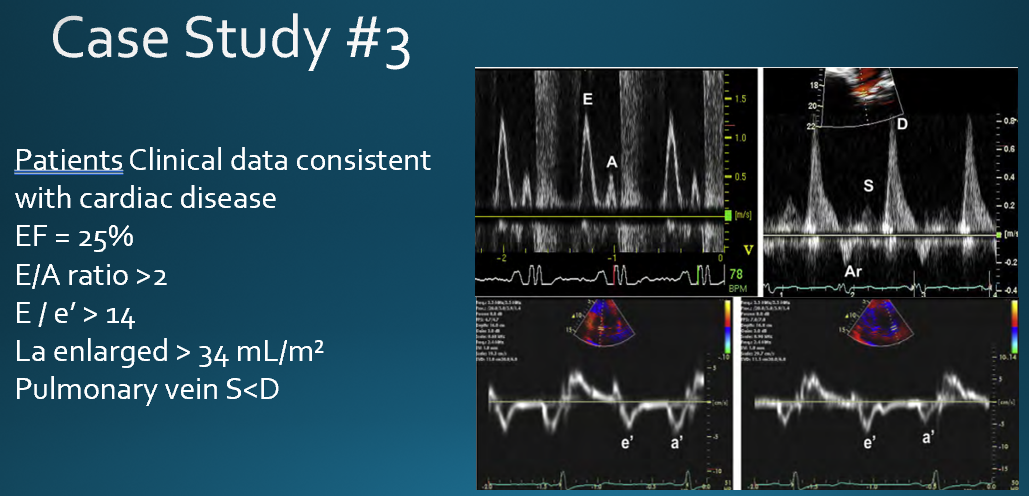

based on what variables is diastolic dysfunction diagnosed?

average e/e’ ratio

annular e’ velocity (Septal e’ velocity or lateral e’ velocity)

LA max volume index

Peak TR velocity

how do the variable indicate diastolic function vs dysfunction?

if less than 2 of the variables are positive → normal diastolic function

2 variables positive → indeterminate

more than 2 variables positive → diastolic dysfunction

A patient's pulsed wave Doppler of the mitral valve had an E/A ratio of 1.5. The patients tissue Doppler had a decreased e' velocity and E/e' ratio >14. What is the most likely diagnosis?

moderate dysfunction

what diastolic pattern is shown here?

severe

deceleraion less than 150

E/A ratio : 2.78